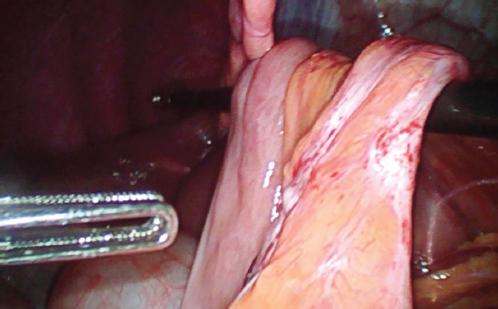

A la exploración, el paciente se encontraba en postura antiálgica, con un abdomen doloroso a la palpación en el mesogastrio, sin distensión ni signos de irritación peritoneal. En la analítica sanguínea se apreciaba neutrofilia (78.5%) sin leucocitosis ni otras alteraciones. Se realizó una tomografía computarizada (TC) de abdomen-pelvis con contraste intravenoso en la que, a nivel del pie de asa, se identificó una angulación y una disminución de calibre de un segmento de intestino delgado en el hipocondrio izquierdo (Fig. 1), junto a signos indirectos de hernia interna, como el «arremolinamiento» de los vasos del meso (Fig. 2). Se practicó una laparoscopia exploradora urgente, en la que se halló una herniación de la casi totalidad del asa alimentaria a través del ojal mesentérico de Petersen (Fig. 3) y un ojal mesentérico del pie de asa de mediano tamaño (Fig. 4). Se realizó reducción del segmento de asa herniado y cierre del ojal con sutura barbada de polipropileno 2/0, y cierre del ojal mesentérico del pie de asa con la misma sutura.

Siempre que se sospeche una hernia interna, aunque las exploraciones complementarias no sean concluyentes, está indicada una laparoscopia exploradora con el objetivo de identificar las brechas mesentéricas, reducir del intestino herniado evaluando su vitalidad y cerrar los defectos mesentéricos con sutura no reabsorbible8. Todos estos pasos se llevaron a cabo en el paciente que presentamos.